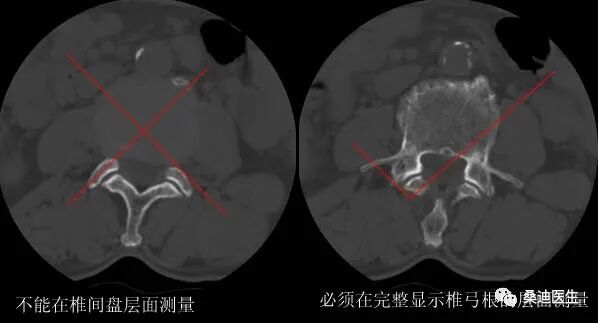

侧隐窝的测量必须满足两个条件:一是必须用骨窗位来测量,二是测量层面必须是完整的椎体层面,即显示出椎弓根的层面。

侧隐窝的测量方法是关节突的内侧缘与椎体后部的连线的长度: